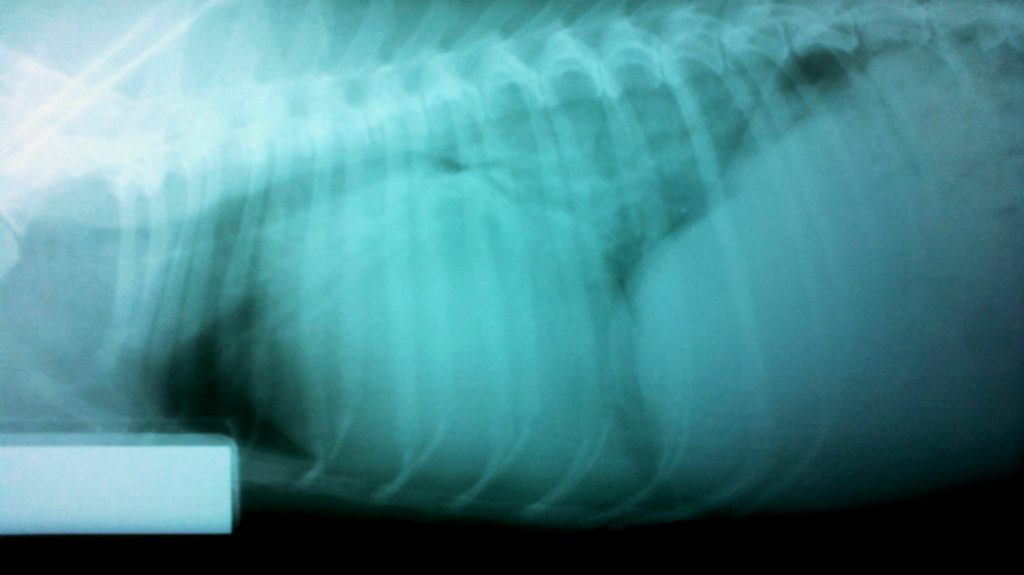

Se toma el ECG adjunto y la radiografía lateral derecha adjunta, no se dispone, por el momento, de más pruebas diagnósticas.

Decúbito lateral derecho

reto veterinario ICC 2015-RX